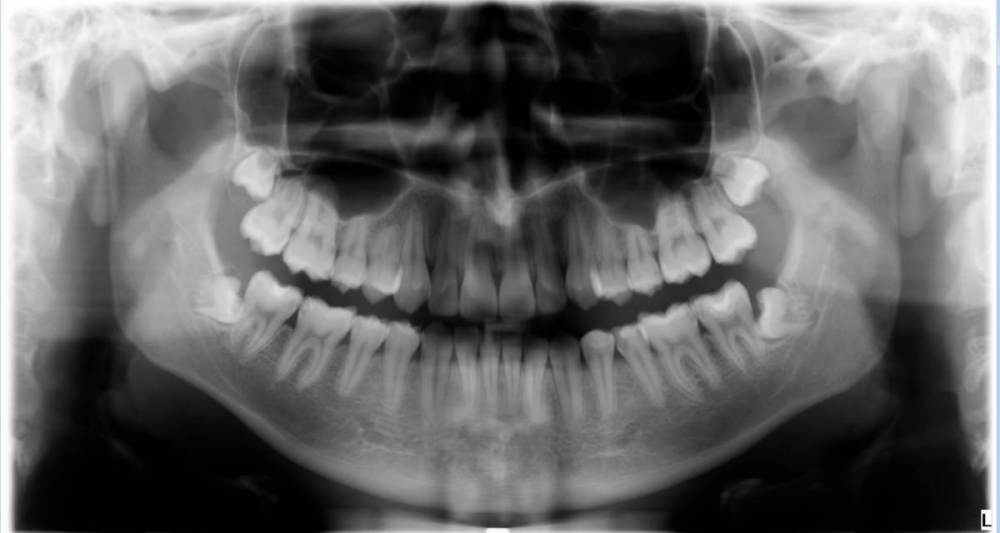

modsamara Опубликовано 12 марта, 2023 Поделиться Опубликовано 12 марта, 2023 Всем добра, подскажите пожалуйста по восьмеркам. 17 лет, недавно было пару дней дискомфортно в нижней челюсти, как будто что-то сдавливало зубной ряд сделал снимок Подскажите, стоит ли вообще удалять нижние и верхние? Для удаления нижних врач планирует пилить челюсть Порекомендуйте к кому обратиться за очной консультацией и удалением - качественным и не очень дорогим:) Ссылка на комментарий

Зубоволок 36 Опубликовано 13 марта, 2023 Поделиться Опубликовано 13 марта, 2023 Добрый день, нижние удалять. Насчёт верхних, скорее всего, так как без нижних в них нет смысла. " Пилить челюсть" - один из возможных вариантов удаления этих зубов, но лучше пилить сам зуб на части. Ссылка на комментарий

modsamara Опубликовано 13 марта, 2023 Автор Поделиться Опубликовано 13 марта, 2023 2 часа назад, Зубоволок 36 сказал: Добрый день, нижние удалять. Насчёт верхних, скорее всего, так как без нижних в них нет смысла. " Пилить челюсть" - один из возможных вариантов удаления этих зубов, но лучше пилить сам зуб на части. ну доктор говорит что и зубы пилить и челюсть я как не спец на снимке вижу что впринципе, если распилить зубы, то они вылезут в имеющиеся отверстия Ссылка на комментарий